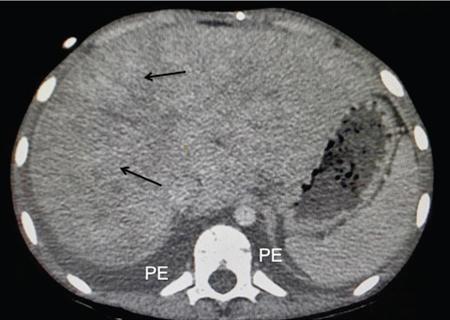

DIFFUSE PARENCHYMAL DISEASES OF THE LIVER Ishan Kumar, Ashish Verma The hepatic parenchyma is the site for multiple essential, interrelated, and complex metabolic activities to assimilate nutrients, detoxify the body, and synthesize vital molecules such as enzymes, hormones, cofactors and essential components of the coagulation pathway. The chemical reactions involved in each of these activities pose a threat to the hepatocytes, which may be damaged leading to the initiation of reparative processes. Further, the liver, being a highly vascular organ with multiple metabolic activities, is liable to be involved in many systemic vascular and metabolic disorders. On one hand, such changes cause healing of the tissue injury, but on the other hand, lead to diffuse parenchymal changes, which may result in suboptimal functioning of the organ. Such a condition is labelled as ‘diffuse liver disease’ and includes (a) diseases caused due to storage of certain chemical products of such chemical reactions labelled as ‘storage disorders’, (b) diseases caused due to reduction of blood flow to the organ, (c) parenchymal injury due to stasis of bile at various levels in the pathway due to varied causes, and (d) involvement of liver in systemic or organ-based inflammatory disorders. The mainstay of diagnosis of diffuse liver diseases is the detection of alterations in the biochemical parameters in blood indicative of liver function, which however is nonspecific to various aetiologies. The diffuse liver diseases in children are quite different from those in the adult population and constitute mainly of congenital or inherited metabolic and vascular diseases as opposed to diseases of acquired aetiologies in the latter population. The gross and microscopic pathological changes are accordingly different in the paediatric population and may be utilized to add specificity to the biochemical indicators as far as aetiological diagnosis is concerned. The invasive and potentially hazardous sampling mandated for histological evaluation of liver parenchyma has been replaced by an array of imaging modalities in recent times. The present chapter presents a review of the currently available imaging modalities (viz. cross-sectional imaging modalities such as ultrasonography, computed tomography [CT] and magnetic resonance [MR] imaging) for evaluation of diffuse liver diseases along with the pertinent imaging features and guidelines for their rational use in various indications. Also a short review of certain key technical and technological details is included. Jaundice and hepatomegaly are the most common clinical manifestations of liver disease. Anorexia is a nonspecific sign, often present in acute or chronic liver disease. Jaundice is a sign of increased bilirubin content in the blood, that can exist in four forms: (i) unconjugated bilirubin bound to albumin, (ii) unbound unconjugated bilirubin, (iii) conjugated bilirubin and (iv) δ fraction. Direct fraction includes both conjugated bilirubin and δ bilirubin. Conjugated hyperbilirubinemia is due to decreased excretion by liver or biliary tract obstruction. Pruritus, spider angioma on face and neck, ascites, portal hypertension, botchy palmer erythema, subcutaneous xanthoma, gastrointestinal (GI) variceal bleed, encephalopathy, renal dysfunction and pulmonary involvement are manifestations of advanced cirrhosis. Evaluation of total serum bilirubin and its fractional analysis into indirect (unconjugated) and direct (conjugated and δ fraction) bilirubin helps to distinguish between elevation caused by haemolysis and that due to hepatic dysfunction or biliary obstruction. Elevations in alkaline phosphatase (ALP), 5′ nucleotidase, and γ-glutamyl transpeptidase (GGT) levels are an indicator of biliary obstruction. However, it should be noted that normal growing children have significant elevations of serum ALP activity. AST (aspartate aminotransferase) and ALT (alanine aminotransferase) are significantly raised in acute hepatitis. ALT rise disproportionate to AST rise is seen in viral hepatitis. A predominant rise in AST is seen in echovirus infection, various metabolic diseases or alcohol-induced hepatitis. These aminotransferases are also elevated in NAFLD/NASH. ALT/AST rise is less marked in chronic liver disease. PT-INR, serum albumin levels can evaluate the hepatic synthesis function. Hypoalbuminemia suggests a bad prognosis. γ-Globulin is elevated in autoimmune hepatitis (AIH). Alpha-fetoprotein is raised in hereditary tyrosinemia or hepatic neoplasms. Indications of liver biopsy in the paediatric age group include neonatal cholestasis, metabolic liver disease, NAFLD, congenital hepatic fibrosis, abnormal biochemical liver tests of unknown aetiology, intestinal failure associated liver disease, acute liver failure and liver tumours. Although biopsy of children and infants is considered a safe procedure, due to incidences of shock, the North American Society for Pediatric Gastroenterology and Nutrition (NASPGHAN) has recommended liver biopsy in children not to be necessarily performed as outpatient procedures. Sonography-guided percutaneous liver biopsy has been reported to be safer, more efficient, more comfortable and only marginally more expensive than blind biopsy. The use of coaxial technique, determination of the number of passes and use of track embolization were at the discretion of the interventional radiologists. In cases of uncorrected PT-INR elevation, transjugular liver biopsy can be performed. Ultrasound (US) is a valuable tool in the diagnosis and management of diffuse liver diseases. It provides useful information about the size, surface, parenchymal architecture, biliary channels and blood flow of the liver. US examination of the liver is performed in the supine position with a convex (5–7.5 MHz) probe. High-frequency (7.5–12 MHz) linear transducers can be used in young infants because of their small size. US examination can be completed with the colour Doppler technique and US elastography, if needed. CT protocol typically requires image acquisition during the multiple phases with a slice thickness of 5 mm or less and a pitch ranging from 1 to 1.5. Contrast injected is 2 mL/kg through manual or mechanical injection. The arterial phase begins at 10–15 seconds and the portal phase is at 20–40 seconds after contrast injection. Equilibrium phase is obtained at 3 minutes, when needed. MRI protocol to evaluate paediatric liver chiefly includes free-breathing sequences, due to the challenge offered by an inadequate breath-hold in these patients. Due to the same reason, motion insensitive single-shot HASTE sequences or motion insensitive T1-weighted spoiled GRE single-shot sequences are also widely utilized in paediatric MR examinations. In slightly older children with a relatively uniform breathing pattern, external trigger signals from a breathing belt, or navigator techniques may be used to overcome motion artefacts from breathing. T1- and T2-weighted turbo spin-echo (TSE) sequences and T2-weighted single-shot sequences in axial and coronal planes are initially acquired to evaluate the anatomy and screen for pathologies. This is followed by a gradient echo (GRE) images to examine vascular structures. Multiecho images with T1-weighting can be acquired to evaluate the fat content of lesions. Contrast-enhanced MRI with intravenous injection of gadolinium (Gd)-based contrast agent is performed as routine in cases with suspected portal hypertension or in any associated suspected neoplastic lesion. This is usually clubbed with MRA for vascular mapping. Arterial phase and portal phase should be acquired 10–15 seconds and 20–30 seconds, respectively after the start of contrast agent injection. GRE T1-weighted sequence should be repeated continuously four or five times to include achieve all phases of liver perfusion. Finally, steady-state imaging should be performed in the equilibrium phase (3 minutes) using T1-weighted and T1-weighted fat-suppressed imaging sequences. MRI contrast media should be administered with caution after evaluation of eGFR, and is safer than the iodinated contrast media needed for CT scan examination, and is hence preferred. Liver size measurement is commonly obtained in one of the two ways (a) an anterior to the posterior measurement of the liver in the midclavicular line, (b) a dome-to-tip longitudinal measurement of the liver in the midclavicular line. Table 9.8.1.1 provides suggested upper limit values of liver and spleen length for various paediatric age groups. Despite advances in 3D US, volume measurements of liver size have not been incorporated in the routine clinical practice because it is time-consuming, requires considerable skill and technically difficult fusion of multiple 3D sweeps. Nonalcoholic fatty liver disease (NAFLD) is referred to as triglyceride accumulation in hepatocytes and encompasses a broad range of clinicopathological entities ranging from simple steatosis, steatohepatitis to cirrhosis. Its worldwide reported prevalence is approximately 2.6%–10% in the general paediatric population and as high as 38% of obese children under the age of 19 years. In India, the reported prevalence is as high as up to 22% in the general paediatric population and up to 45% in obese and overweight children. Hepatic steatosis currently is the most common cause of chronic liver disease in paediatric patients. Table 9.8.1.2 highlights the causes of hepatic steatosis in paediatric age group. The pattern of injury is similar to alcoholic liver disease. Nonalcoholic steatohepatitis (NASH) constitutes a subset of NAFLD, ranging from simple steatosis to inflammation and fibrosis. NASH in children has two distinct histological subtypes. Type 1 NASH resembles adult subtype with macrovesicular steatosis, lobular inflammation, and ballooning degeneration and perisinusoidal fibrosis. Type 2 NASH shows steatosis with portal fibrosis and is present in younger children with increased severity of obesity. ALT can be normal in 20% of the patient with NAFLD and liver biopsy is the gold standard for diagnosis as well as a semiquantitative assessment of disease severity. In clinical practice, the diagnosis and monitoring of NAFLD largely rely on ultrasonography. Grade I fatty liver refers to diffusely hyperechoic parenchyma with a well-visualized diaphragm (Fig 9.8.1). Bright liver with loss of periportal echogenicity and indistinctly visualized vessels is referred to as grade II and blurring of the diaphragm is classified as grade III fatty liver. Limitations of the US are lack of objective quantification and diminished sensitivity in cases where biopsy-proven steatosis ratio is less than 30%. Moreover, hepatic fibrosis and inflammation in cases of NASH are sonographically indistinguishable from simple steatosis. Contrast-enhanced US can diagnose the presence of fibrosis in NAFLD, which is evident from the decreased accumulation of microbubbles in the liver parenchyma. The distinction between hepatic steatosis and fibrosis is important clinically, as fibrosis can progress to cirrhosis if left untreated. US elastography has emerged as a promising technique to screen the children with NAFLD to look for ongoing steatohepatitis/fibrosis. Transient elastography is the most popular elastography technique which has shown excellent accuracy in the adult population with chronic hepatitis. However, its accuracy in NAFLD is significantly lower and the data of effectiveness in the paediatric population is limited. Acoustic radiation force impulse imaging (ARFI) has been shown to have a good correlation with AST/ALT ratios in obese children with NAFLD. An ARFI elastography value of >1.19 m/s predicts NASH-related hepatic changes in these patients while a value >1.75 m/s is suggestive of cirrhosis. Another study on shear-wave elastography has shown a high correlation in paediatric NAFLD patients with biopsy-proven hepatic fibrosis. A value of >5.1 kPa strongly predicts the presence of fibrosis whereas a value of >6.7 kPa is suggestive of stage ≥F2 fibrosis (Brunt scoring system). CT is a common modality utilized for assessment of hepatic pathologies, however is seldom used for assessment of NAFLD because of the risk of ionizing radiation. On noncontrast CT, liver attenuation <40 HU or hepatic attenuation 10 HU lesser than that of the spleen is considered as a sign of steatosis. Recent literature advocates the utilization of MRI in the evaluation of NAFLD. Fat imparts high signal intensity to the liver parenchyma on T1-weighted spin-echo MR images while it is mildly hyper- to hypointense on T2-weighted images. Conventional spin-echo imaging is relatively insensitive to mild-to-moderate fatty infiltration of the liver. The most commonly employed technique for detection of steatosis is chemical shift imaging (Dixon technique or dual-echo method) which utilizes two sets of gradient-echo images of the liver, that is in-phase and out-of-phase. On in-phase echo-time, water and fat signals add whereas, on out-of-phase echo-time, water and fat signals cancel each other. In nonfatty livers, the signal intensity of the liver parenchyma is unchanged between in- and opposed-phase images whereas a fatty liver shows a notable reduction of signal intensity on the opposed-phase images. Iron deposition in the liver can interfere with the assessment of steatosis. MR spectroscopy has been one of the most reliable techniques for the evaluation of hepatic steatosis (Fig 9.8.1.2). Protons in water molecules resonate at 4.7 ppm while that in triglyceride molecules resonate predominantly at 1.3 ppm. Other smaller lipid peaks can be obtained at 0.9, 2.0, 2.2 and 5.3 ppm. In a healthy nonfatty liver no triglyceride peak should be present. The presence of fat can allow measurement of area under water peak versus area under fat peaks to procure hepatic fat fraction. Proton density fat fraction (PDFF) measurement by MRI is another promising objective technique for quantification of steatosis in the paediatric patient. PDFF is the ratio of the density of mobile fat protons and the total density of protons including that from triglycerides and mobile water. Magnetic resonance elastography (MRE) is suggested as a noninvasive tool to evaluate liver stiffness that correlates with the degree of fibrosis. The technique is based on measuring the propagation of shear waves through liver parenchyma. A cut-off value for liver stiffness of 2.27 kPa has been suggested to predict Ludwig grade 2 or higher fibrosis. The technique depends on measuring the propagation of shear waves through the hepatic parenchymal fibrosis and differentiation of low-grade fibrosis from high-grade and also it may be feasible to distinguish steatosis from steatohepatitis. Success rate and accuracy of MRE is higher than US-based transient elastography. Cirrhosis is referred to as diffuse end-stage chronic liver disease characterized histologically by fibrosis and nodular regeneration, along with the disorganization of liver architecture. Although various underlying aetiology can lead to cirrhosis in children (Table 9.8.1.3), the most common causes in India are posthepatitic cirrhosis, Wilson’s disease (WD), AIH, biliary cirrhosis, biliary atresia and other metabolic diseases. In 5%–15% cases, the cause of cirrhosis may remain undetermined and is known as cryptogenic cirrhosis. Imaging is central to the diagnosis and management of children with cirrhosis (Fig 9.8.1.3). The role of imaging extends from diagnosis of cirrhosis to identification of complications and detection and characterization of nodules in cirrhotic liver. The imaging findings consist of changes in liver morphology, parenchyma and contour of the liver, vascular changes including portal hypertension, liver nodules and other complications of cirrhosis. Cirrhosis can lead to volume redistribution, which can be evaluated using either the US, CT, or MRI. Signs of early cirrhosis are atrophy of the segment IV, evident on imaging by increased fat segment IV and portal vein and between segment IV and left lobe. Signs of advanced cirrhosis are atrophy of the right lobe and segment IV with compensatory hypertrophy of left lobe and caudate lobe and fatty expansion of GB fossa. In some patients, a sharp notch is seen in the posterior surface of the liver (segment VI/VII). Some aetiology of cirrhosis may have different patterns of volume redistribution such as atrophy of left lobe and posterior segments in primary sclerosing cholangitis, diffuse hypertrophy in primary biliary cirrhosis, and absence of caudate hypertrophy in WD. The US can detect changes in liver segmental volumes based on linear measurements. C/RL (caudate/right lobe) ratio >0.65 calculated by comparing the transverse length of caudate and right lobe at the portal bifurcation, is a sign of cirrhosis. CT/MRI-based segmental volumetric analysis can reflect the morphological changes more effectively. Liver parenchyma in children appears as isoechoic to hypoechoic compared to the renal cortex in the US. The neonatal liver may reveal a bright echotexture. Hyperechoic parenchyma is seen in the fatty liver or liver fibrosis. Cirrhosis is seen as coarse and heterogeneous parenchyma. The liver surface in normal children appears as a hyperechoic, straight and regular line. The liver surface with diffuse irregularity or nodular surface is present in cirrhosis. CT and MRI in frank cirrhosis can reveal heterogeneous parenchyma along with the irregular surface. Diagnosis of early cirrhosis and fibrosis cannot be reliably made by the US where parenchyma may appear within normal limits. Similarly, CT and conventional MR sequences are also insensitive in early cirrhosis although early fibrosis can be seen as T1 hypointense/T2 hyperintense areas on MR and may show subtle enhancement. These T2 hyperintensities can be present as perilobular bands, perivascular cuffing, bands surrounding regenerative nodules, patchy fibrotic areas, or diffuse reticulation (honeycomb pattern). The role of US elastography and MR elastography is increasing in paediatric liver diseases for the detection of fibrosis and early cirrhosis and has been discussed in the previous section. US examination should be complimented with Doppler of the portal vein and hepatic veins if US features are suspicious of cirrhotic or fibrotic changes. The diameter of the portal vein increases with age. The mean diameter of the portal vein is 3.5 mm in children <5 years, 6.3 mm in 6–12-year old children, and 7–11 mm in >12-year-old children. Portal vein diameter is increased in portal hypertension; however, no reliable age-dependent cut-off values exist for the PV diameter in the diagnosis of portal hypertension in paediatric patients. Peak portal vein velocity in the paediatric age group is usually above 20 cm/s in a nonfasting child (15 cm/s in term neonate) along with some respiratory undulation. Peak portal vein velocity <16 cm/s in the paediatric age group is suggestive of portal hypertension. In term neonates, the values are above 15 cm/s. An increase in pulsatility of the portal vein (PI < 0.5) suggests portal hypertension. Reversal of portal vein flow (hepatofugal flow), presence of periportal collaterals or portal cavernoma, umbilical vein recanalization and various other collaterals are other signs of portal hypertension. Hepatic veins should be evaluated to rule out Budd–Chiari syndrome. CT or MR portal venography can comprehensively assess the extent and anatomical location of portosystemic collateral vessels in children with liver cirrhosis. Four groups of collateral channels can be identified: (a) periportal collaterals and portal cavernoma, (b) collaterals draining into SVC, that is left gastric vein (coronary vein), short gastric vein, oesophageal and paraoesophageal collaterals, (c) collaterals draining into IVC such as paraumbilical vein and abdominal wall collaterals, splenorenal and gastrorenal collateral, (d) mesenteric, retroperitoneal and haemorrhoidal collaterals. Various nodules can be seen in the cirrhotic liver including regenerative nodules, dysplastic nodules and HCC. The US is not sensitive in identifying these nodules and high-frequency linear-array transducer can contribute to their detection. CT and preferably MR can be used to characterize these nodules. Table 9.8.1.4 summarizes the imaging findings of these nodules on CT and MRI. It should be noted that HCC is rare in young children although it has been reported in children younger than 5 years in progressive familial intrahepatic cholestasis (PFIC) and Byler disease, biliary atresia. Recognizing the need for paediatric-specific guidelines for standardized interpretation and reporting CT and MR, ACR – LI-RADS (Liver Imaging Reporting and Data System) committee has convened the Pediatric LI-RADS Working Group in 2017. Hepatorenal fibrocystic diseases (HRFCDs) are developmental abnormalities of the liver and portobiliary system with associated fibrocystic degeneration of the kidneys. HRFCDs belong to the larger group of disorders collectively referred to as ‘ciliopathies’ a term describing the group of disorders affecting primary cilia which are an organelle present within the cholangiocytes. The ciliopathies in the liver is manifested as ductal plate malformation. Ductal plate is the embryonic precursor of the intrahepatic bile ducts and their abnormal development leads to cyst formation and alteration in portal venous development. Two major disorders are included in these malformations: (i) congenital hepatic fibrosis (affecting small intrahepatic ducts) and (ii) Caroli’s disease (affecting larger ducts). A combination of the CHF and CD is known as Caroli’s syndrome. Liver function test results in DPM may remain normal or be only modestly elevated. Few of congenital cystic liver pathologies are not associated with ciliopathies, such as autosomal-dominant polycystic liver disease (ADPLD) and portal fibrosis associated with congenital disorder of glycosylation (CDG) type Ib. Tables 9.8.1.5 and 9.8.1.6 innumerate the renal diseases and syndromes associated with ciliopathies. Carbohydrate-deficient glycoprotein syndrome type 1b Renal–hepatic–pancreatic dysplasia Oral–facial–digital syndrome type I US is the first-line modality, which can detect the distinctive morphological features of CHF that includes left lobe (segments II and III) hypertrophy, normal or hypertrophies segment IV, and atrophied right lobe. Preservation of the volume of the left medial segment is a feature that distinguishes CHF from cirrhosis resulting from viral hepatitis. The US can also detect changes in parenchymal echotexture, presence of splenomegaly, and can identify the evidence of cystic disease in the kidneys. Portal hypertension is one of the common presenting features of CHF despite normal hepatic lobular architecture and normal hepatic function. Application of the Doppler technique can detect the features of portal hypertension and cavernomatous transformation of the portal vein which can be present in up to 50% of the cases of DPM. The portal vein shows abnormalities in its ramification pattern with numerous, hypoplastic branches which are closely spaced, referred to as ‘pollard willow’ pattern. Studies have also shown enlarged hepatic artery and regenerative nodules in the arterialized hepatic parenchyma. In cases of Caroli’s syndrome, the US can easily identify cystic lesions or dilated intrahepatic bile ducts and can detect the stones in the ducts. Intraductal bridging (echogenic septa) can be seen traversing the dilated biliary duct lumen. Occasionally, the US can identify small portal venous branches surrounded by dilated biliary duct. Because of the absence of risks of ionizing radiation, US is the modality of choice in these children for long-term follow-up. CT can comprehensively demonstrate the morphological changes of CHF. Segmental computer-aided volumetric analysis of the hepatic parenchyma can identify the volume distribution with higher accuracy compared to the US. CT can also detect the parenchymal changes with higher sensitivity than the US. CT in these patients shows heterogeneously enhancing liver parenchyma, volume changes, and complete vascular mapping of the abdomen in cases of portal hypertension, identifying the portosystemic collaterals. Periportal cuffing can be identified on CT, indicative of periportal fibrosis. In Caroli’s disease, CT shows segmental and noncontinuous, saccular or fusiform dilatation of intrahepatic biliary radicals with the central enhancing dot representing portal vein branches (Fig 9.8.1.4). CT can identify the communication of the cyst with IHBD, differentiating them from PCLD. CT can also better detect the complications of CD such as cholangitis abscesses and cholangiocarcinoma. Seven per cent of the patients of CD can develop cholangiocarcinoma. MRI and MRCP seem to be a sensitive method for revealing biliary and renal abnormalities associated with congenital hepatic fibrosis and CD, even when sonography findings are normal (Fig 9.8.1.5). The parenchymal changes and heterogeneous architecture along with periportal fibrosis can be demonstrated on T2-weighted images, revealing hyperintensity along the portal vein and its branches. Regenerative nodules can be identified on T2-weighted and contrast-enhanced MRI. MRCP can delineate the communication between the cystic lesions and the biliary tree in cases of CD. Contrast-enhanced MRI can aid in the detection of complicating malignancies which can have a wide range of radiological appearances such as focal hepatic mass, intraductal mass, or biliary stricture. Multiplanar capability of MRI can enable its utility for preoperative planning in the affected children obviating the need for invasive preoperative cholangiogram to demonstrate the anatomy of the biliary tree. The differential diagnosis of Caroli’s disease is ADPLD, Von Meyerberg complex, choledochal cyst, sclerosing cholangitis, recurrent pyogenic cholangitis and peribiliary cysts. PCLD is seen on imaging as more than 20 round and smooth cysts without any communication with the biliary tree. Biliary hamartoma (Von Meyerberg complex) are seen as multiple/unique round uniform small cysts measuring 1–3 mm located close to portal tracts. Recurrent pyogenic cholangitis presenting with intra- and extrahepatic biliary dilatation is the most difficult diagnosis to exclude on imaging, however, the presence of saccular dilatation favours the diagnosis of Caroli’s disease. It should be noted that up to 20% of the cases of Caroli’s disease may have associated extrahepatic bile duct dilatation mimicking choledochal cyst and Caroli’s disease may even coexist with choledochal cyst. The presence of diffuse fusiform dilatation of the extrahepatic duct with less than 3 cm diameter combined with the characteristic intrahepatic ductal findings may help differentiate patients with Caroli’s disease from patients with a choledochal cyst associated with intrahepatic biliary dilatation. Routinely 1–2 mg of iron is absorbed by the intestine in a healthy child. Iron is recycled by extravascular haemolysis in the liver to meet the required amount (25 mg) in the spleen and bone marrow through Kupffer cells. Excess iron is bound to ferritin and hemosiderin in the hepatocytes. Excess iron in the body may be deposited in the liver, spleen, lymph nodes, pancreas, kidneys, pituitary, myocardium and GI tract. Up to 10–20 mg of excess iron does not cause tissue damage, in which case the term haemosiderosis is applied. Functional and structural impairment of the tissues occurs if the iron load (50–60 g) exceeds the compensatory mechanisms. In these cases, the term hemochromatosis is applied. Primary hemochromatosis is a genetic disorder occurring through mutation in the HPE gene which causes increased absorption of iron through the intestine. The secondary nongenetic form is more common and is caused due to multiple blood transfusions (transfusional haemosiderosis) in haematological disorders such as myelodysplastic syndrome, aplastic anaemia, beta-thalassemia major (transfusion haemosiderosis). Prolonged and excessive iron deposition can lead to endocrine abnormality, cardiac failure and liver parenchymal disease. Liver biopsy was considered as a reference standard for the detection and quantification of iron overload in hepatic parenchyma. However, it is largely replaced by radiological techniques because of the invasive nature and small size of sampled tissue while doing a single-site biopsy. The US cannot detect the features of iron overload in the liver parenchyma; however, it can be useful in detecting the complications of iron overload such as cirrhosis, hepatocellular carcinoma (HCC) or features of portal hypertension. CT scan is also of limited utility in hemochromatosis. Attenuation of >65 HU (15–130) with low attenuation of hepatic vessels relative to liver parenchyma on noncontrast CT is suggestive of iron overload, however can also be seen in WD, glycogen storage disorder, long-term amiodarone administration. MRI is the primary radiological modality used for diagnosis of iron distribution, quantification and monitoring of treatment response in liver iron overload (Fig 9.8.1.6). Various MRI techniques have been devised for iron overload estimation. This technique compares the signal intensity of liver parenchyma with the signal intensity of paraspinal muscles, which are assumed to be unaffected by iron content. GRE sequences are obtained with TR of 120 ms, flip angle 200, and varying TE of 2, 4, 9, 14 and 20 ms. Three ROIs of 1–2 cm are drawn in liver parenchyma and one on each paraspinal muscles. Liver iron concentration can then be obtained using a free online calculator provided by the University of Renne. Images are obtained with TR 2500 ms, flip angle 900 and variable TE of 6, 9, 12, 15, 18 ms. The images can be used to draw automated ROI covering the right lobe of the liver (excluding vessels) in the largest area and a T2 map of the same images can be generated. The technique quantifies the T2 shortening due to proton exchange between bulk water and exchangeable protons in ferritin. T2* takes into account the contributions of the T2 (1/R2) effects and the microscopic inhomogeneities introduced in (B0) by the hemosiderin clusters. For T2* measurement single breath-hold multiecho GRE sequences with TR of 25 ms, flip angle of 20 degrees, TEs every 0.25 ms from 0.8 to 4.8 ms are obtained. R2 * (1/T2*) values can be generated with ROI drawn from a single midhepatic section by drawing an ROI following the boundaries of the liver and excluding hilar vessels. Liver iron concentration can be obtained using a formula: [Fe] = 0.202 + 0.0254 R2*. This technique detects the enhancement in the local magnetic field caused due to ferritin or hemosiderin using a 3D breath-hold multiecho GRE sequence with the use of chemical shift–encoded water/fat separation, T2*/R2* mapping, and B0 field mapping. A quantitative susceptibility map of the parenchyma is generated. A local relative susceptibility value (ΔB0) is obtained drawing ROI which is expressed in parts per million (ppm), related to local iron deposition. With the ongoing research, stress is being placed upon the multiparametric quantitative MR imaging protocol which includes MR elastography (for fibrosis), multiecho chemical shift–encoded GRE to measure proton-density fat fraction (for steatosis quantification) and R2* relaxometry (for iron overload estimation). Hepatic iron overload has been shown to predispose to the development of HCC in the younger age group. The detection of HCC in the setting of iron overload is less difficult on T2-weighted sequences because the presence of iron behaves like a nonspecific contrast medium, such as superparamagnetic iron oxide (SPIO). However, care should be taken while evaluating these lesions, which may appear like hepatic cyst or haemangioma. Any nodule detected in these patients should be evaluated and characterized by the use of intravenous gadolinium contrast. The liver processes various metabolic processes of the body and hence it can be affected by multiple inherited metabolic disorders. The affection of the liver in these disorders may be in the form of hepatomegaly, cholestasis, acute liver failure or hepatic encephalopathy. WD is an autosomal recessive disorder of copper metabolism, first described in 1912 by Samuel Kinnier Wilson. The primary defect is a genetic abnormality located at chromosome 13 and q14.3, coding for copper-transporting P-type ATPase. An average diet contains 3–5 mg copper, 40% of which is absorbed in the upper GI tract and which is almost completely excreted in bile. The genetic defect leads to abnormality in this excretory function that leads to copper accumulation in the liver and other organs and tissues including brain and cornea. Liver disease in WD can range from asymptomatic transaminasemia, acute or chronic hepatitis, fulminant hepatic failure, and cirrhosis. WD can be misdiagnosed as AIH because both can result in similar autoantibodies. Imaging findings of liver manifestations can be categorized into four groups: (i) morphological changes, (ii) parenchymal changes, (iii) perihepatic changes, (iii) other findings. On CT, copper deposition in the liver may present with increased attenuation of the hepatic parenchyma, however, associated hepatic steatosis can decrease the overall attenuation which is within normal limits in most of the patients. Contrast-enhanced CT can show hypodense as well as hyperdense nodules and surface irregularity. The disappearance of hyperdense nodules has been documented after penicillamine therapy. Various MRI features of liver disease in WD has been described in the literature that includes (a) T1 hyperintense/T2 hypointense nodules (2 mm to 1 cm), (b) T1 hypointense nodules, (c) multiple hyperintense septae leading to ‘honeycomb pattern’, (d) high-intensity septa, (e) absence of parenchymal changes on MR. 31P MR spectroscopy of the liver in WD can show elevated phosphomonoester (PME) resonance and reduced phosphodiester (PDE) resonance, which have been shown to normalize after penicillamine and vitamin K therapy. Gaucher disease (GD) results from a deficiency of lysosomal enzyme β-glucocerebrosidase leading to the accumulation of ‘Gaucher cells’ in various organs. Imaging can help in the detection and characterization of liver infiltration, hepatomegaly, fibrosis, cirrhosis, iron deposition and HCC, all of which are associated with GD. On imaging, hepatosplenomegaly is the hallmark of GD (Fig 9.8.1.7). Recent literature recommends the utilization of CT or MRI over the US for volumetric assessment of liver and spleen sizes in GD with the expression of liver volume as multiples of normal volume (MN). Weight-based formula is used for calculation of liver and spleen volumes: normal liver volume (mL) = 25 × weight (in kg) ; and normal spleen volume (mL) = 2 × weight (in kg). A target liver volume of 1–1.5 MN and a spleen volume of 2–8 is aimed by the therapeutic regimens. On MRI, low ADC of liver and spleen indicates greater infiltration and worse prognosis, with ADC values correlating with chitotriosidase levels. Fibrosis can be detected and quantified using US shear-wave elastography, MR elastography, and nonimaging–based transient elastography. Studies have indicated the presence of liver iron deposition in GD due to associated hyperferritinemia, which can be quantified using R2* relaxometry. Hepatic nodules can be identified on imaging on GD. Most commonly these nodules represent a focal accumulation of Gaucher cells and are known as ‘Gaucheroma’. These lesions are hyperechoic on the US, hypoattenuating on CT, T1 hypointense/T2 heterogeneous nodules on MRI. These lesions do not merit biopsy; however, care should be taken to identify the lesions suspicious for HCC, that is large, irregular, hypoechoic, hypervascular lesions, which mandate further evaluation by multiphasic contrast CT or MRI. Besides the liver, evaluation of abdominal imaging should attempt to detect changes in spleen and visualized bones. GD in the spleen can manifest with splenomegaly, fibrosis, nodules, subcapsular infarcts and splenic necrosis. Osseous features of GD are osteopenia, osteonecrosis, pathological vertebral fractures and Erlenmeyer flask deformity. These are a group of disorders caused by defects in metabolism or storage of glycogen which broadly present with hepatic, myopathic, cardiac or other manifestations. GSD type I (Von Girke disease) presents with hepatic involvement. The US in these patients shows hyperechoic liver parenchyma because of fatty replacement and glycogen deposition. CT shows variable attenuation because hepatic attenuation is increased by glycogen and decreased by steatosis. There is a well-known association with GSD and hepatic tumours such as adenoma, focal nodular hyperplasia and HCC (rare). Adenomas are the most common tumours in GSD which show variable echogenicity. These lesions may contain fat, haemorrhage, or rarely dystrophic calcifications. A fat component can be detected using chemical shift MRI. These lesions should be monitored serially and malignancy should be suspected in case of rapid growth. α1-Antitrypsin deficiency is a rare autosomal recessive disorder that can cause chronic severe paediatric liver disease. In infants, this disorder can have a presentation similar to biliary atresia or idiopathic neonatal hepatitis. Moreover, scintigraphy cannot distinguish between biliary atresia, because similar to atresia, it can show uptake by hepatocytes and absence of biliary excretion due to paucity of lobular biliary ducts. The US in the neonatal period can help distinguish between the two, as it shows normal gallbladder and hepatic parenchyma. Older children may show imaging evidence of hepatic fibrosis or cirrhosis. MR elastography in this disorder is accurate for identifying fibrosis with a cut-off value of >3 kPa predictive of fibrosis. Various systemic illnesses can present with liver disease. The table summarizes the hepatic manifestations of various systemic liver diseases. TABLE 9.8.1.7 Paediatric diffuse liver diseases though forming a small subset of overall morbidity in children pose a formidable challenge for diagnosis as most cases present at a relatively early age. Imaging in these cases aims to make an aetiological diagnosis and rule out any associated complications, as the initial diagnosis is usually established by the biochemical analysis of liver function. Screening sonography usually forms the initial screening modality with MRI being the next stop problem-solving modality. CT scan has taken a back seat in current practice due to radiation exposure and the need to inject iodinated contrast media, both of which can be obviated by MRI. The former modality however remains essential in case an interventional procedure to treat portal hypertension is contemplated or percutaneous sampling from areas difficult to access by sonography is to be done. With the availability of an array of imaging modalities, it remains essential for an imaging expert to be clear as far as the choice of modality and order of its usage during the course on management is involved so that the most optimum imaging protocol can be offered to the patient. PEDIATRIC BENIGN HEPATIC MASSES (INCLUDING INFECTIONS) Kushaljit Singh Sodhi, Anmol Bhatia, Akshay Kumar Saxena Liver neoplasms constitute around 2% of all neoplasms seen in the pediatric population, and around 6% of the total abdominal neoplasms. Only one-third of the liver tumours in children are benign, while two-thirds are malignant. Benign hepatic tumours in children include lesions which are specific to children like mesenchymal hamartomas and vascular tumours, and the lesions that are also seen in adult population, such as adenoma, focal nodular hyperplasia (FNH) and nodular regenerative hyperplasia (NRH). Further, benign hepatic lesions affecting children include a wide variety of infections of bacterial, fungal and parasitic origin. In the present chapter, we will be discussing about the benign hepatic tumours and hepatic infections commonly seen in the pediatric population. A wide variation has been reported in the use of terminology for the hepatic vascular malformations in literature. According to the standard nomenclature adopted by the International Society for the Study of Vascular Anomalies (ISSVA), liver vascular tumours in children are termed as liver hemangioma. Liver hemangiomas in children are classified as infantile and congenital. Infantile hemangiomas usually begin to grow after birth, continue to grow during the first year of life and enter an involuting phase between 1 and 7 years. These tumours are positive for glucose transporter-1 protein (Glut-1), a protein that facilitates the transport of glucose across erythrocyte cell membranes. On the other hand, congenital hemangiomas are fully developed at birth and are characterized by Glut-1 negativity. These are further subdivided into a rapidly involuting group and a noninvoluting group, with some overlap between these groups. Hemangioma is a model of the angiogenesis concept proposed by Folkman et al and its development is related to a combination of upregulation of factors that promote angiogenesis and downregulation of its inhibitors. Most of these tumours are diagnosed in the first year of life, with these being slightly more common in females. Most commonly, these present as an asymptomatic mass in abdomen; however, associated life-threatening presenting complications have also been reported. These include high-output cardiac failure as a result of large arteriovenous shunts or Kasabach–Merritt syndrome of coagulopathy, severe hypothyroidism and acute hemoperitoneum due to tumour rupture. Lesions can be focal, multifocal or diffuse. Multifocal lesions are usually small and homogenous in appearance, while larger lesions may show areas of hemorrhage, calcification, fibrosis and necrosis. The liver is grossly enlarged in diffuse disease, which may cause mass effect on surrounding organs and vessels. Multifocal lesions frequently are associated with multiple cutaneous infantile hemangiomas with a Glut-1 positive marker. Biopsy of these masses should be avoided as there is a risk of bleeding, and the diagnosis is made based on typical imaging features and involution at follow-up. Well-defined hypoechoic or hyperechoic lesion, which may show heterogenous echotexture because of central hemorrhage/necrosis. A variety of flow patterns may be seen on colour Doppler due to the presence of shunts which may be portosystemic, or arteriovenous shunts. The hepatic arteries and veins usually enlarged, with large feeding arteries and draining veins seen surrounding as well as within the lesions. The lesions are usually hypoattenuating to the liver parenchyma with speckled calcifications seen in up to 50% of cases. The enhancement pattern is similar to that of hemangioma in adults and shows intense peripheral nodular enhancement on arterial phase with progressive centripetal filling on venous and delayed phases. Small lesions usually show intense and uniform enhancement (Fig. 9.8.2.1). The lesions show hypointense signal on T1-weighted images (T1WI) and hyperintense signal on T2-weighted images (T2WI). The tumour shows internal vascular flow voids and centripetal enhancement (Fig. 9.8.2.2). Heterogeneous signal may be seen due to presence of hemorrhage, thrombosis and necrosis. Calcifications may be seen in about 16% of cases.